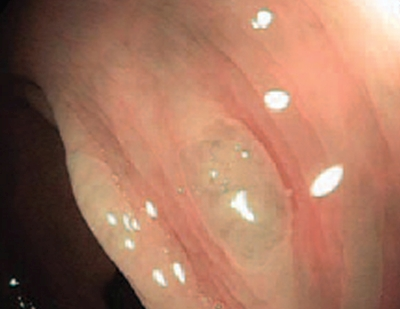

Тип 3 — характерний для злоякісної пухлини (ЗМ)

Колір: темніший за навколишнє, коричневий, іноді зі світлішими плямами

Судини: ділянки з перерваними або відсутніми судинами

Поверхня: аморфна або без малюнка на поверхні